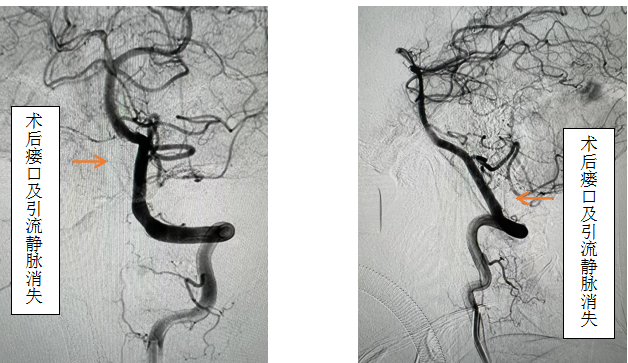

,效果欠佳。入院时已经行走困难,行颈椎核磁见颈椎蛛网膜下腔异常信号影,请神经外科会诊后考虑硬脊膜动静脉瘘可能性大,转入神外后立即由李帅主治医师行全脊髓血管造影,见“左侧椎动脉V4段发出脑膜支,其远端分支供血形成硬脊膜动静脉瘘,瘘口位于枕骨大孔区,经延髓背侧及腹侧向下引流至胸2椎体节段”。缪星宇主任主持全科病例讨论,讨论考虑患者经脊髓血管造影后诊断明确,手术指征明确,可行硬脊膜动静脉瘘介入栓塞术或开颅阻断术。术中可采取“高压锅”技术防止栓塞胶的返流,降低微导管的到位要求,降低返流空间的要求,使得返流空间安全可控,缩短注胶时间,增加胶的弥散效率,从一定程度上提高栓塞比例,增加患者的安全性。如介入微导管到位困难,可以考虑开颅阻断瘘口,但瘘口位置距离呼吸中枢延髓较近、术中风险大且术后患者恢复时间长。科室讨论后决定利用黑料网先进的复合手术室,首先采用第一方案“高压锅”技术使胶完全封堵瘘口,若不能到位或完全封堵,则采用第二方案,转为开颅阻断瘘口。手术当日,由黄卫东主任医师和李帅主治医师操作,第一根栓塞微导管顺利到达瘘口,第二根微导管接近栓塞微导管后使用弹簧圈顺利形成高压锅塞子,经第一根微导管注入栓塞胶,射线透视下见栓塞胶按预期流向瘘口,栓塞满意后造影示瘘口及引流静脉均未见显影,手术成功。术后患者恢复良好,第二天即下床活动,下肢活动明显恢复,5天后步行出院。